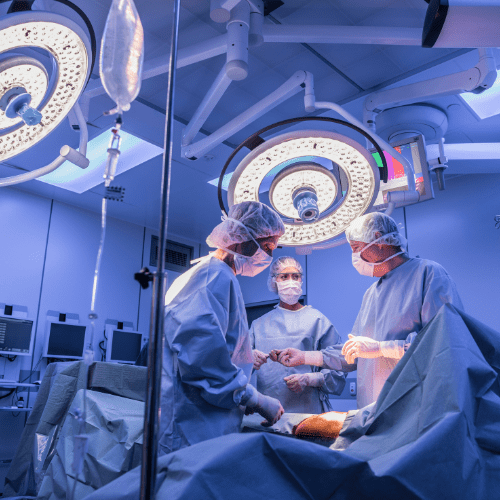

Operation Theatre

Heal and Health Hospitals features modular operation theatres with modern sterilization and monitoring systems. Our surgical team performs a wide range of procedures with precision, following the highest safety and hygiene protocols.